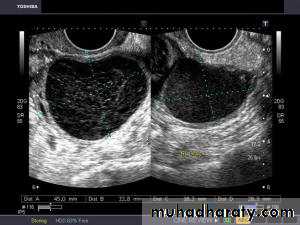

Lt. adnexal cystic mass- Luteal cyst(Lt. ovary):• Functional cysts of the ovary – Corpus Luteum cysts

Rt. ovarian simple cyst: